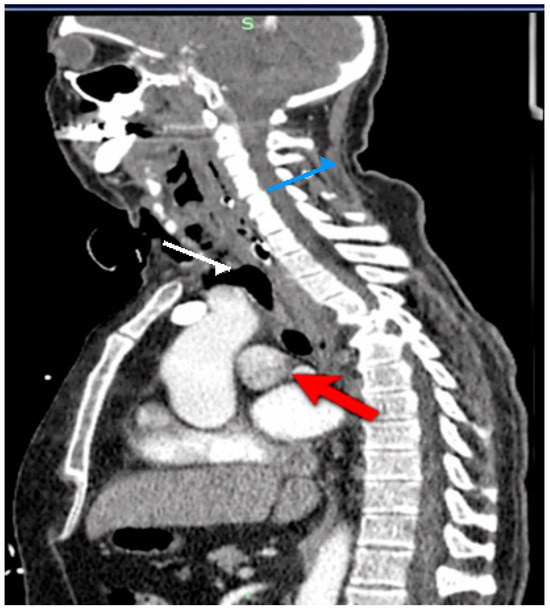

Background: Upper esophageal perforations are life-threatening conditions associated with a high risk of mediastinitis, sepsis, and multiorgan failure. Standard management often requires extensive surgical intervention, which carries substantial morbidity. Methods: We report the case of a 56-year-old male with an iatrogenic cervical esophageal perforation complicated by cervicomediastinal abscess formation. Due to anatomical constraints preventing standard endoluminal approaches, a hybrid organ-preserving strategy was employed, consisting of surgical drainage combined with an externally adapted vacuum-assisted closure (VAC) system applied adjacent to the esophageal defect. Results: The patient demonstrated progressive clinical improvement without the need for esophageal diversion or major reconstructive surgery. Inflammatory markers were monitored serially and showed a downward trend, serving as adjunctive indicators of treatment response. The esophageal defect healed successfully, was confirmed radiologically, and no treatment-related complications were observed. Conclusions: This case suggests that externally adapted VAC therapy may represent a potential organ-preserving option in selected patients with complex cervical esophageal perforations when conventional techniques are not feasible. Further studies are required to validate this approach. Full article

Figure 1